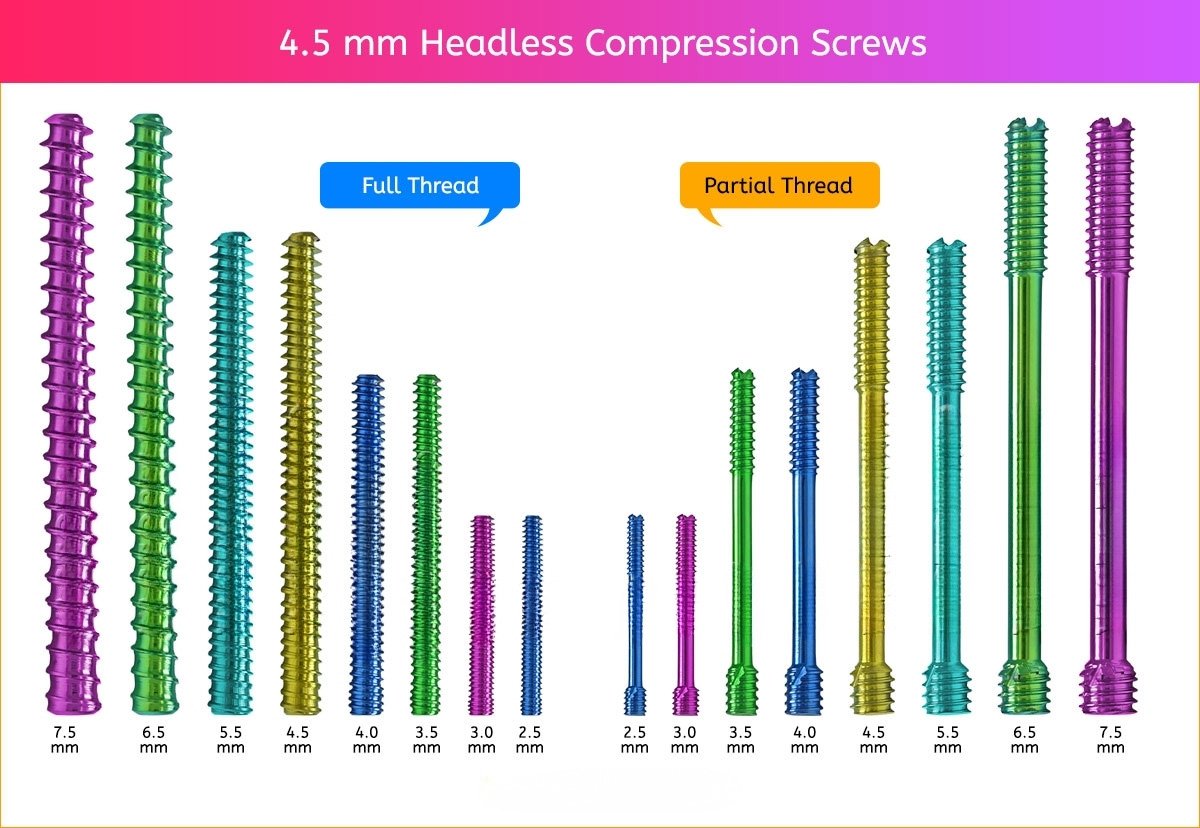

4.5 mm Headless Compression Screw

4.5 mm Screws Length

8mm, 10mm, 12mm, 14mm, 16mm, 18mm, 20mm, 22mm, 24mm, 26mm, 28mm, 30mm, 32mm, 34mm, 36mm, 38mm, 40mm, 42mm, 44mm, 46mm, 48mm, 50mm, 55mm, 60mm, 65mm, 70mm, 75mm and 80mm.